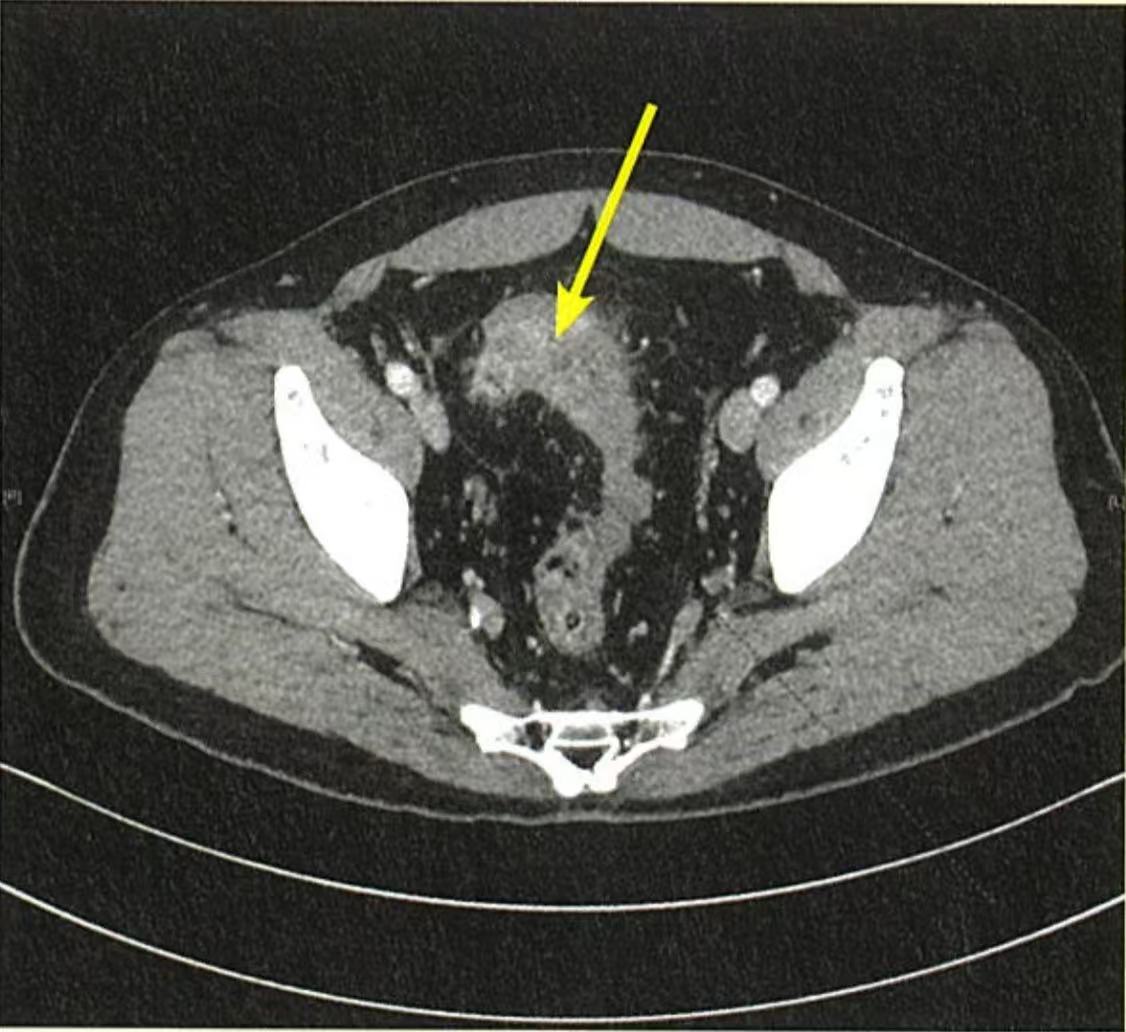

急性闌尾炎初期有可能先出現上腹痛,主要是腸道神經線的根源接近上腹腔,因發炎而引致內臟疼痛;與此同時,由於腹腔內有一塊與胃部連接的大網膜,具有固定和保護腹腔器官的功能。發炎初期,網膜會包圍着發炎的位置,以試圖控制發炎情況,因而令胃部產生拉扯感覺或疼痛。病人可能在數天後,才因劇痛延伸至右下腹而求醫,確診為急性闌尾炎時有機會已出現膿瘡。因此,如懷疑腹痛與急性闌尾炎有關,醫生會為病人安排腹部電腦掃描,以評估及確定發炎位置及是否已有穿孔、膿瘡等併發症。

在這種情況下,針對因急性闌尾炎引致炎性腫塊的病人,醫生會先處方抗生素把感染控制下來,病人須留院接受經靜脈注射抗生素,觀察一星期可出院,繼續接受約兩星期的口服抗生素治療。完成抗生素療程後約六至八個星期,病人須再接受腹部電腦掃描檢查,經醫生評估炎性腫塊的情況及確定闌尾位置後,才予以手術切除。